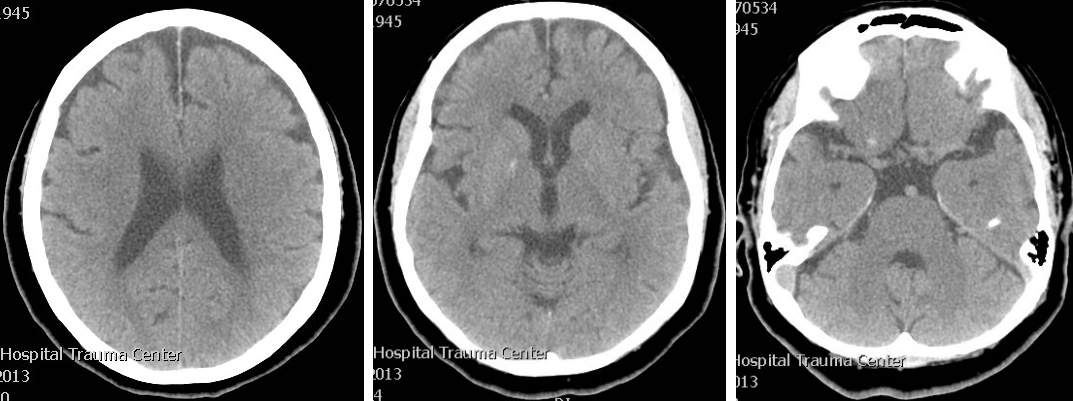

This is the case of a 57-year-old Indian right-handed woman who was known to have hypertension and ischemic heart disease and was on regular medication for these comorbids. On the day of presentation she woke up well and after 2 waking hours she started having involuntary movements on the right side of the body. This occurred 5–7 times and was described by the patient like some tightening spell which would persist for 5–10 sec and then it relieved by itself. This was followed by a weakness on the right side of the body which was so severe that she could not move out of bed. After half an hour the weakness started improving. When she reached hospital, her condition had much improved. On examination she was mildly slow in mental processing, but GCS (Glasgow Coma Scale) score was 15/15. She had mild dysarthria but speech assessment and cranial nerves were normal. In the motor system she had mild weakness with power of grade 4+/5 in the right sided limbs, both proximally and distally, and mild hypotonia on the right side. Power on the left side was normal. Reflexes were normal and symmetrical on both sides. The other examination results was unremarkable. We did CT brain which was normal (Figure 1 [Fig. 1]). Preliminarily we thought of tonic seizure disorder followed by Todd’s paralysis because we did not witness that episode and were dependant on history. We thought of stroke/transient ischemic attacks and discussed it with the family. At that time deficit was minimal and history was also suggesting Todd’s paralysis, so the unanimous decision was made not to treat as stroke and just to observe for seizure. Therefore she was not given thrombolytic therapy, however we loaded her with 300 mg Aspirin.

Figure 1: Brain CT of the patient taken at presentation which shows only basal ganglia calcification. No early ischemic changes, no hyperdense artery sign.